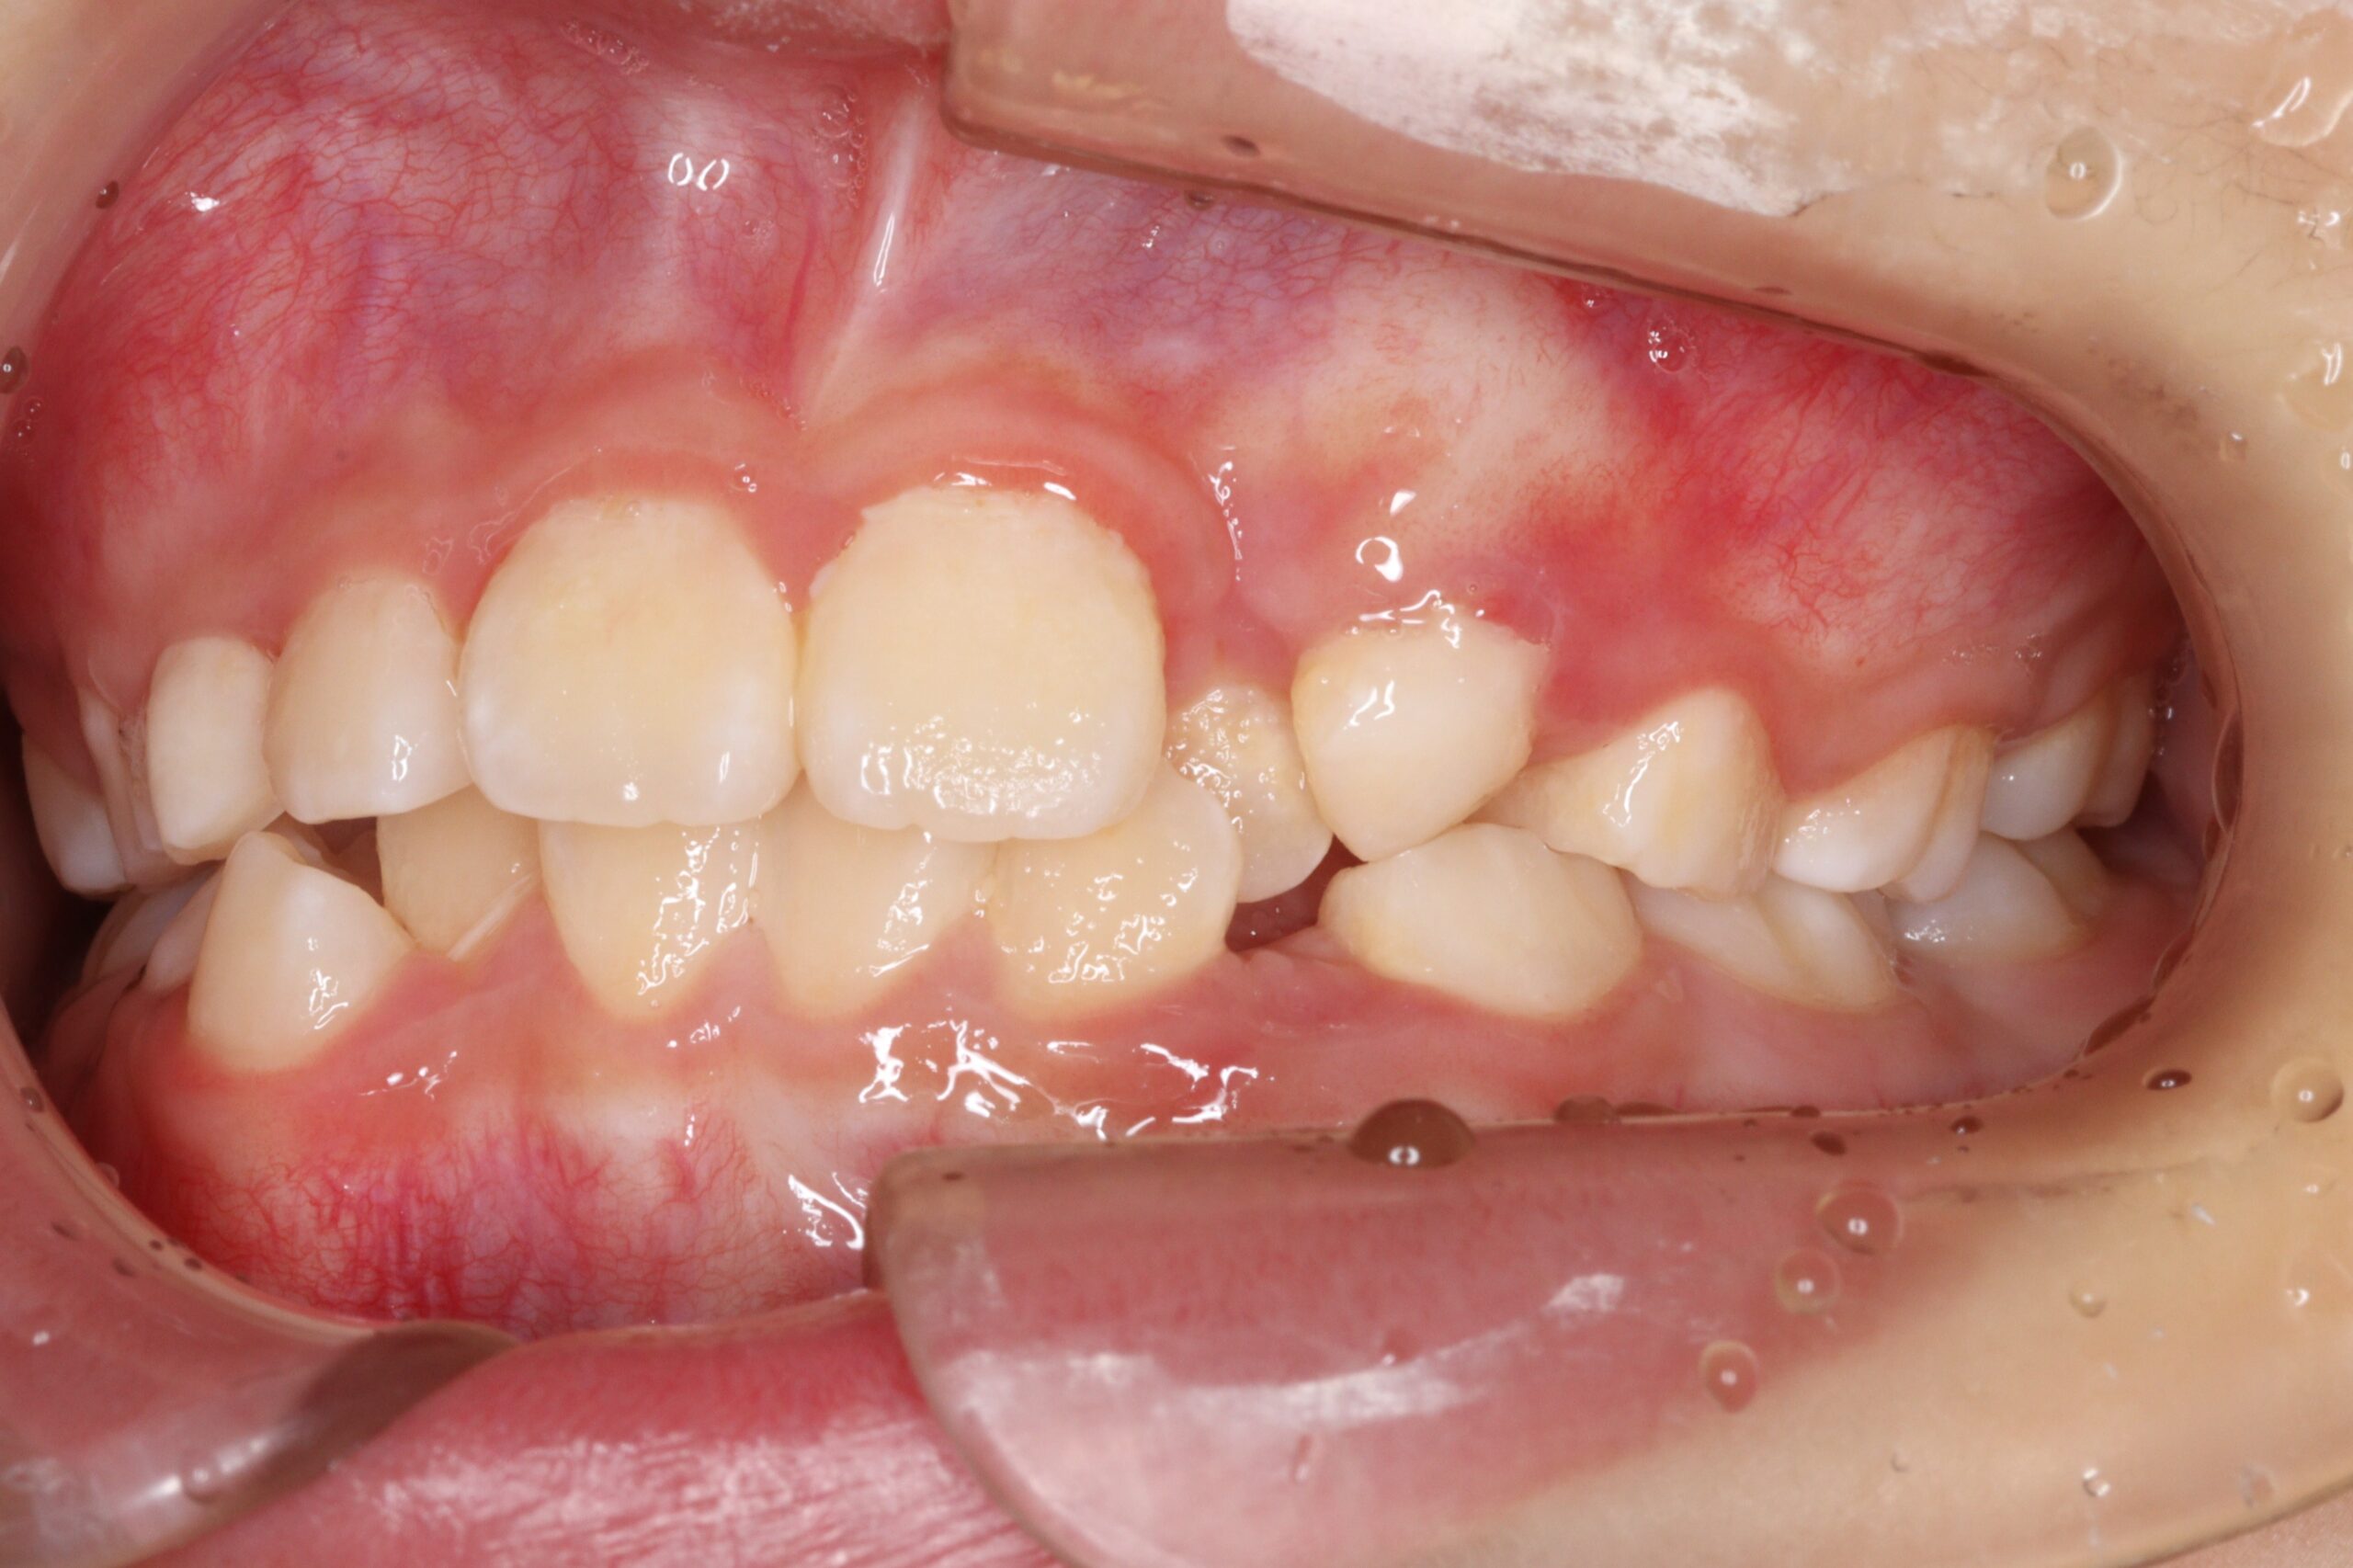

矯正術前:右側

矯正術後:右側